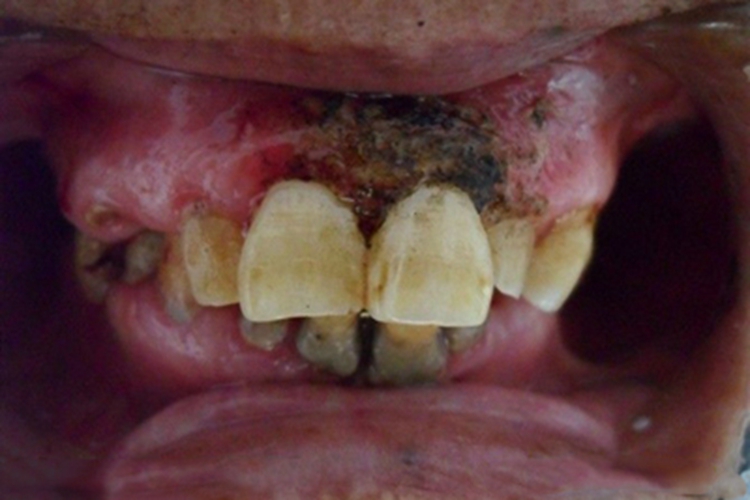

坏死性溃疡性龈口炎为急性感染性炎症,发病急骤,症状显着,可累及舌头、牙龈等位置,主要特征为局部形成穿掘性坏死性溃疡,边缘不整齐,表面有灰黑色、灰黄色假膜,并向周围及深层侵犯。

患者可自觉疼痛,因疼痛而影响进食、说话,常伴有发热、头痛、乏力等症状。